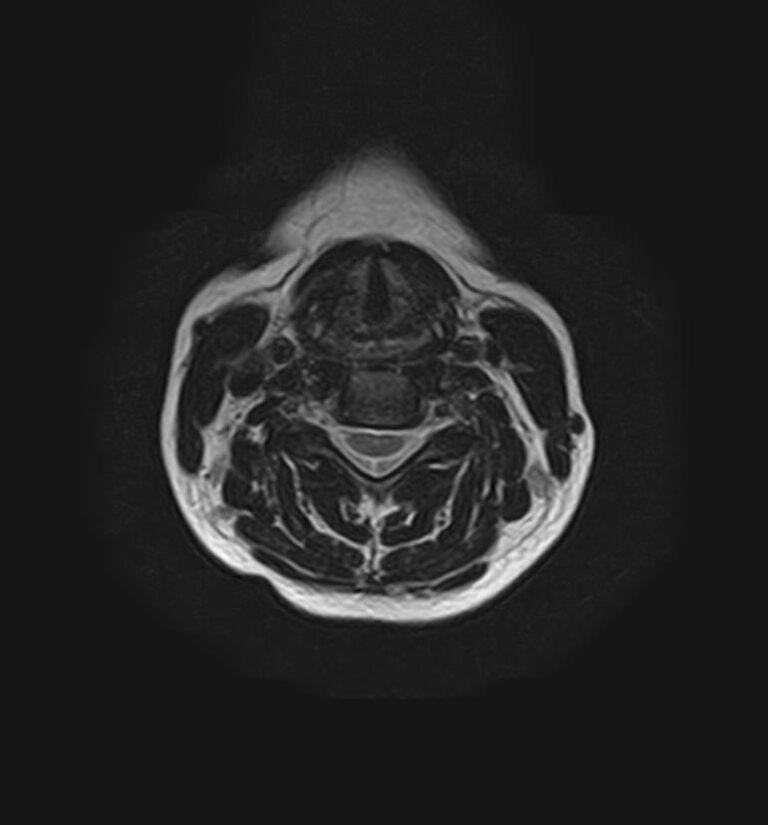

Для того, чтобы оценить состояние шейных позвонков с прилегающими тканями и одновременно визуализировать крупные сосуды шеи, в нашей клинике выполняется комплексное обследование, включающее два протокола: МРТ шейного отдела позвоночника и МР-ангиографию шеи.

В клинике «Доступная медицина» комплексное обследование шейного отдела позвоночника одновременно с МР-ангиографией шеи проводится на новейшем высокопольном томографе экспертного уровня TOSHIBA VANTAGE TITAN 1,5 Тесла, который производит послойное сканирование исследуемой зоны в разных плоскостях, затем при помощи компьютерных программ преобразует полученные данные в трехмерные изображения шейного отдела позвоночника и кровеносной системы, что позволяет проводить точную диагностику и назначать пациенту своевременное лечение.

Что покажет МРТ шейного отдела позвоночника + МР-ангиография шеи

Данное комплексное исследование позволяет проводить диагностику следующих патологических состояний:

• дегенеративно-дистрофические заболевания шейного отдела позвоночника (межпозвонковые грыжи, протрузии, остеохондроз, спондилоартроз, спондилез, унковертебральный артроз, сколиоз, усиленный или выпрямленный лордоз как нарушение статической функции позвоночника);

• травмы позвоночника, спинного мозга, связочного аппарата, близлежащих мягких тканей;

• опухоли спинного мозга, костей, нервных корешков или мягких тканей, окружающих позвоночник;

• инфекционные и воспалительные заболевания позвоночника и спинного мозга;

• демиелинизирующие заболевания спинного мозга;

• аномалии развития позвоночника;

• участки сужения, извитость, образование петель и перегибов сосудов;

• ангиомы, сосудистые мальформации.